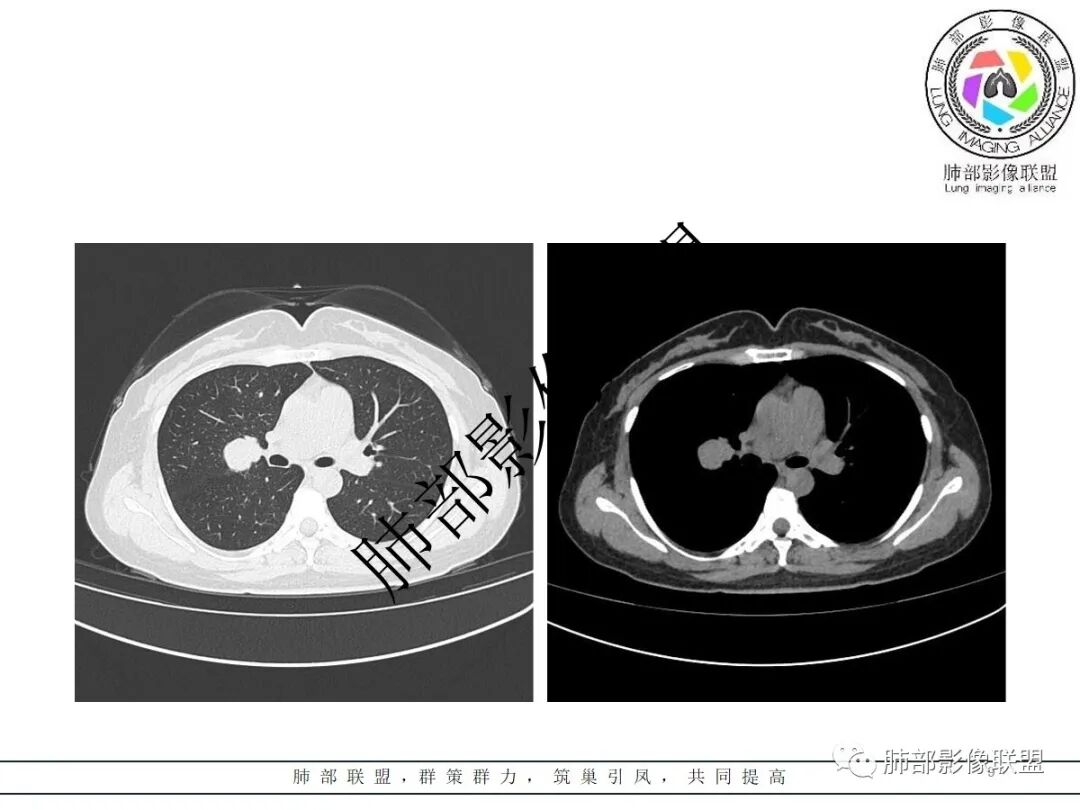

右肺门类圆形实性肿块,边缘光滑,无分叶毛刺,跨叶,推移血管,密度均匀,增强延迟强化相对明显,未见坏死及血管造影征。

右肺中叶跨叶间裂球形影,边缘光滑,均匀强化,可见血管贴边征,血管包绕征,周围有磨玻璃影,考虑硬化性肺细胞瘤,但是需排除淋巴瘤

右近肺门类圆形肿块,边缘光滑,密度均匀,压迫邻近肺动脉,跨叶间裂,持续不均匀强化,内见血管影,肺门纵隔淋巴结未见肿大,考虑PSP,鉴别类癌。

2.右肺水平叶裂斜叶裂肺门交界区类椭圆形块影,表面光整,未见分叶毛刺及棘状突起,未见邻近结构牵拉。与邻近支气管无关联。

3.病灶密度均匀,未见液化坏死、钙化及脂肪低密度。轻度强化,可见纤细血管影蜿蜒穿行。右肺动脉推移变形,未见侵入或充盈缺损。

4.灶周未见磨玻璃晕或极低密度影环绕。右肺下叶背段胸膜下见微小实性密度结节影,边界清楚。